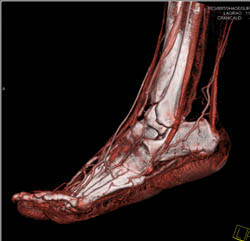

Coalition of Talus and Calcaneus